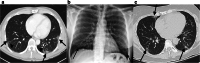

Methods: From 03/01/2020-03/20/2020, a retrospective review of all patients with suspected COVID-19 on imaging was performed. Imaging was interpreted by a board-certified, fellowship-trained radiologist. Patients were excluded if COVID-19 infection was suspected at the time of presentation, was the reason for imaging, or if any lower respiratory symptoms were present.

Results: Eight patients with suspected COVID-19 infection on imaging were encountered. Seven patients received testing due to suspicious imaging findings with subsequent lab-confirmed COVID-19. No patients endorsed prior exposure to COVID-19 or recent international travel. COVID-19 was suggested in six patients incidentally on abdominal CT and two on chest radiography. At the time of presentation, no patients were febrile, and seven endorsed gastrointestinal symptoms. Five COVID-19 patients eventually developed respiratory symptoms and required intubation. Two patients expired during the admission.